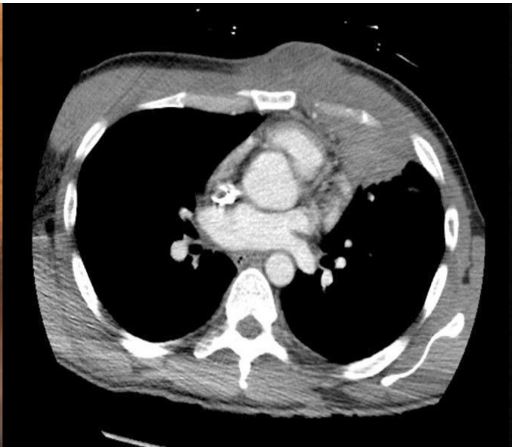

Computed Tomography (CT) of the chest showed a consolidation within the lingula with extension into the anterior chest wall, and a 2 x 5.7 cm soft tissue chest wall fluid collection (Figure 2). Magnetic Resonance Imaging (MRI) brain showed innumerable enhancing intraparenchymal and leptomeningeal/ependymal lesions and enhancement within the right mastoid and below the skull base (Figure 3A). On second night of hospitalization, he developed a fever of 102.3o F. After chest wall abscess was aspirated, he was started on isoniazid, rifampin, pyrazinamide, ethambutol, azithromycin, linezolid, cefoxitin, amikacin and dexamethasone for suspicion of possible mycobacterium infection. Chest wall lesion was also biopsied, and preliminary pathology review showed foamy histiocytes and no granulomas. Transthoracic and transesophageal echocardiogram revealed a small mitral valve vegetation. Culture from chest wall aspirate grew a Gram-positive rod anaerobe after 6 days of incubation, subsequently identified as Actinomyces meyeri by Matrix-Assisted Laser Desorption/Ionization-Time of Flight (MALDI-TOF) mass spectrometry. Fusobacterium necrophorum (beta-lactamase negativefi) also grew on culture and later identified. 16S ribosomal RNA testing showed minor abundance of Aggregatibacter actinomycetemcomitans, Fusobacterium nucleatum, Ralstonia pickettii, Methylbacterium radiotolerans, Caulobacter spp, Novosphingobium spp, and Pseudomonas japonica. Final pathology review of chest wall lesion showed acute and chronic inflammation with prominent histiocytic infiltrates. Gram, acid-fast bacillus, Fite, Giemsa, and periodic acid-Schiff stains did not reveal any microorganisms.

Figure 1: CT chest showing right lung pneumothorax, hemothorax, and subcutaneous emphysema.